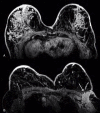

Eccrine porocarcinoma is a rare skin adnexal malignant neoplasm that may arise from a pre-existing benign eccrine poroma or without a predisposing factor. It is a highly invasive neoplasm and has a strong metastatic potential. The most frequently affected organs are the lymph nodes and rarely solid organs such as the liver, lungs and breast. We report a case of a woman with a history of surgically treated eccrine porocarcinoma that a year later presented with multiple lesions in both breasts and axillary lymphadenopathies. After a detailed imaging investigation, the diagnosis of metastatic lesions from porocarcinoma was made. To our knowledge, until the moment, only one case of breast metastasis of eccrine porocarcinoma has been reported in the literature.